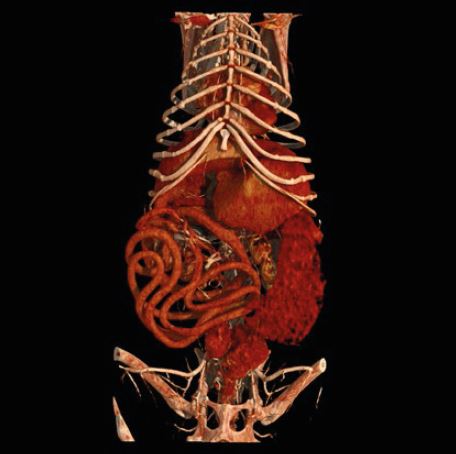

Global Illumination - це нова революційна технологія 3D/4D рендерингу, яка допомагає створити більш фотореалістичне зображення анатомії. Редагуйте, сегментуйте та фіксуйте фотореалістичні

зображення для покращення лікування пацієнтів та передопераційного планування.